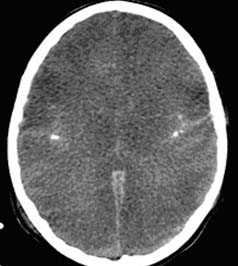

ж) Ушибы коры. Ушибы коры являются следствием кровоизлияния в результате удара мозга о череп. В связи с этим они часто встречаются в лобных и височных полюсах, часто связаны с вдавленными переломами черепа и являются наиболее распространенными паренхиматозными поражениями.

Ключевые данные визуализации:

- Данные КТ на ранней стадии могут быть нормальными.

- На неконтрастной КТ ушибы выглядят как гетерогенные гиперденсные области в ткани головного мозга с кровью и отеком.

- Отек более выражен на последующих КТ.

- Наиболее чувствительным методом в диагностике ушибов является МРТ.